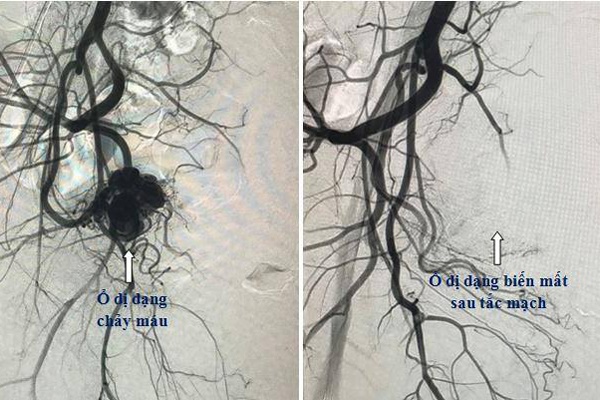

Hình ảnh búi dị dạng gây chảy máu trong động mạch tử cung của bệnh nhân

Người bệnh đã được chụp cắt lớp vi tính để chẩn đoán nguồn gốc gây chảy máu, phát hiện dị dạng, giả phình động mạch tử cung, đây là nguyên nhân gây vỡ và làm chảy máu liên tục, gây mất máu cho người bệnh.

Theo BS Lục, với các trường hợp như chị Ngân, phương pháp điều trị là phẫu thuật thắt động mạch hoặc cắt bỏ tử cung thì hiện nay, với nền y học hiện đại, kỹ thuật can thiệp mạch được ứng dụng và là lựa chọn đầu tiên và hiệu quả nhất.

Theo đó, bác sĩ dùng ống thông và dây dẫn tiếp cận với vị trí dị dạng mạch để nút ổ dị dạng bằng các vật liệu gây tắc mạch. Thời gian thực hiện phẫu thuật chỉ mất 30 phút đến 1 giờ. Đây cũng là thuật can thiệp ít xâm lấn nên bệnh nhân không phải nằm viện lâu.